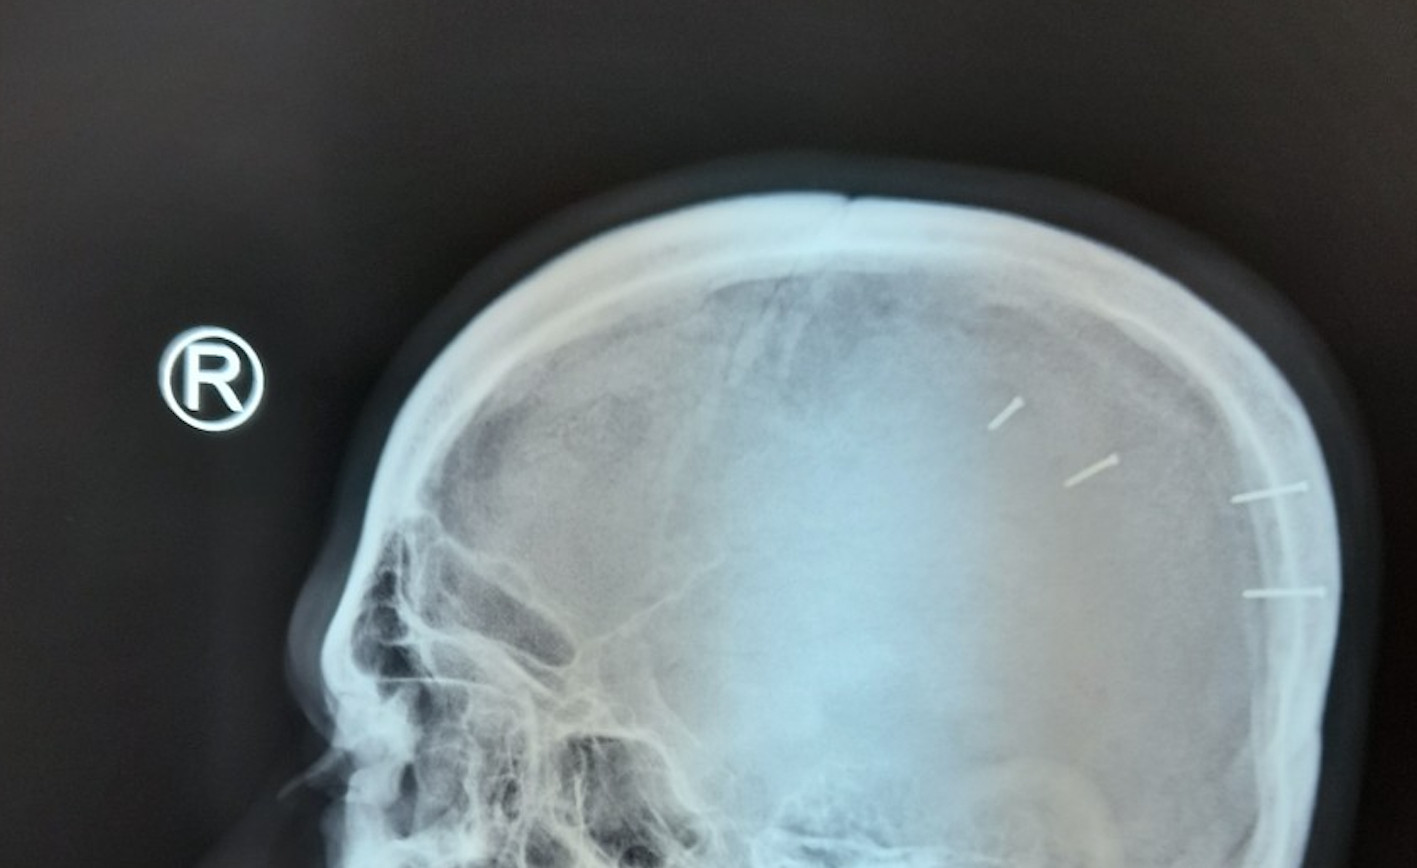

Sau khi chụp X-quang vùng đầu và qua lời kể của anh H., các bác sĩ xác định trong hộp sọ bệnh nhân này có dị vật là 4 cây đinh sắt dài 1,5 cm, đường kính khoảng 2 mm, nằm ở vùng thái dương bên trái.

Tiến hành phẫu thuật, các bác sĩ đã gắp ra được 4 cây đinh, bệnh nhân có dấu hiệu xuất huyết não nhẹ.